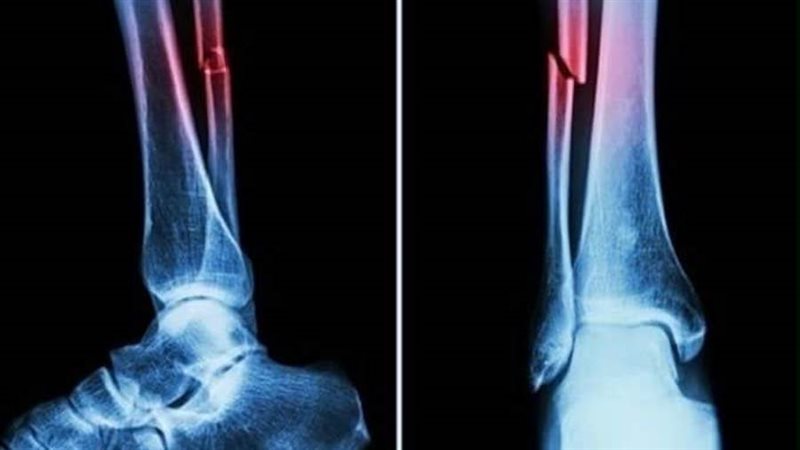

غراء العظام.. اختراع صيني يعالج الكسور في ثلاث دقائق

أعلن فريق بحثي في مقاطعة تشجيانج شرقي الصين عن منتج طبي جديد، "غراء عظمي" قادر على علاج الكسور وإعادة ربط شظايا العظام في ثلاث دقائق فقط، في خطوة وصفت بأنها اختراق علمي في عالم جراحة العظام، بحسب قناة "NDTV".

أكدت الاختبارات المعملية أن Bone-02 حقق نتائج جيدة من حيث السلامة والفعالية. في إحدى التجارب، أُجريت العملية في أقل من 180ثانية "ثلاث دقائق"، بينما استغرقت طرق العلاج التقليدية وقتًا طويلاً لزرع الشرائح الفولاذية.